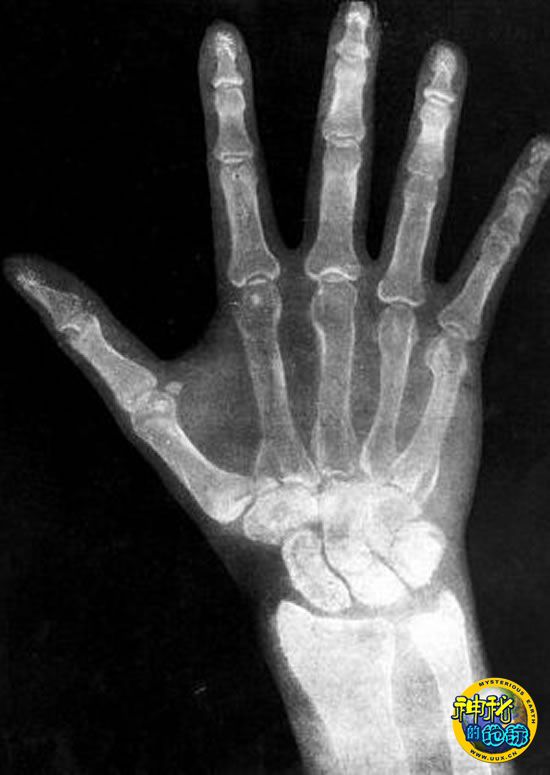

X射线

X辐射是高频电磁辐射的一种。X光可穿透固体,在医学、考古学和天文学方面有非常广泛的应用。德国物理学家伦琴(Wilhelm Conrad Rontgen)第一个发现了这种新射线,并把这种射线标注为“X”,以示它是一种未知射线。这一发现让他在1901年获得一生中的第一个诺贝尔奖。

英国科学博物馆医学馆副馆长卡蒂·马格斯(Katie Maggs)说:“在该馆百年庆典上看到X光机让人难以置信的发展得到公众的认可,我感到非常兴奋。X光从根本上改变了我们对这个世界的看法和认识,尤其是我们的身体。”